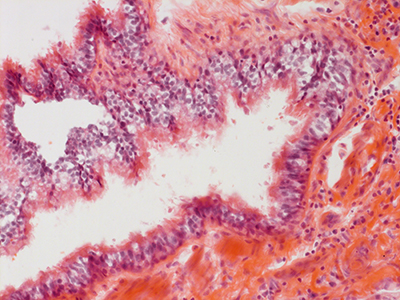

31 Year Old Adult Human Lung D003 H&E